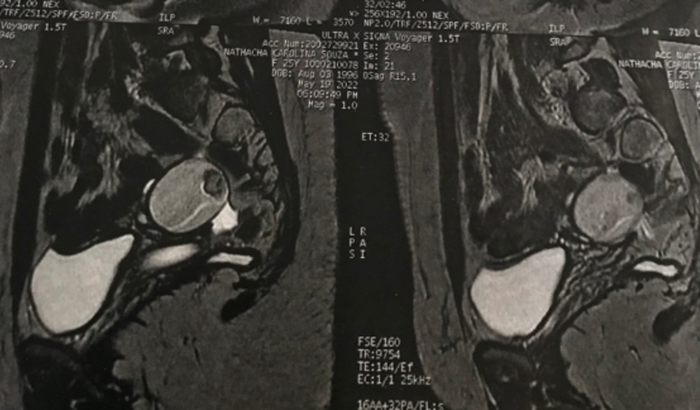

Me chamo Nathacha Carolina Souza Baia, a pouco tempo descobri que possuo um Teratoma no ovário direito, me encontro desempregada no momento portando criei essa vaquinha para arrecadar o valor da cirurgia, que fica R$6000,00 e será realizada no Hospital de Base de São José do Rio Preto. Desde já agradeço muito quem me ajudar.